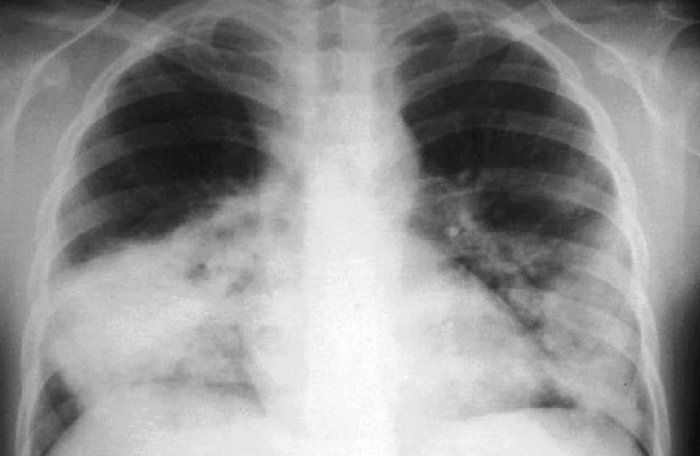

白肺:双肺叶或单侧呈“白化”现象,白色部分占据70%以上的面积,意味着肺部有炎症,有渗出物或积液,多见老年人,慢病人群,高烧数日不退人群等等。